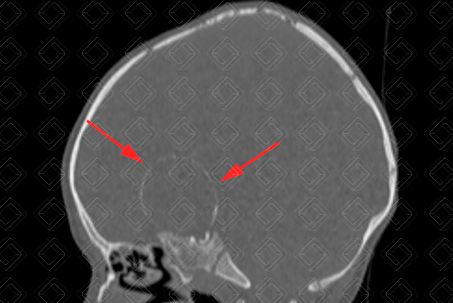

Texto alternativo para a imagem Figuras 1 e 2. Créditos: Dra. Elazir Mota - Rio de Janeiro/RJ

Descrição das figuras 1 e 2: Tomografia computadorizada de crânio evidenciando lesão selar e suprasselar predominantemente heterogênea, predominantemente hipodensa, com calcificação parietal, melhor apreciada na janela óssea (setas vermelhas).